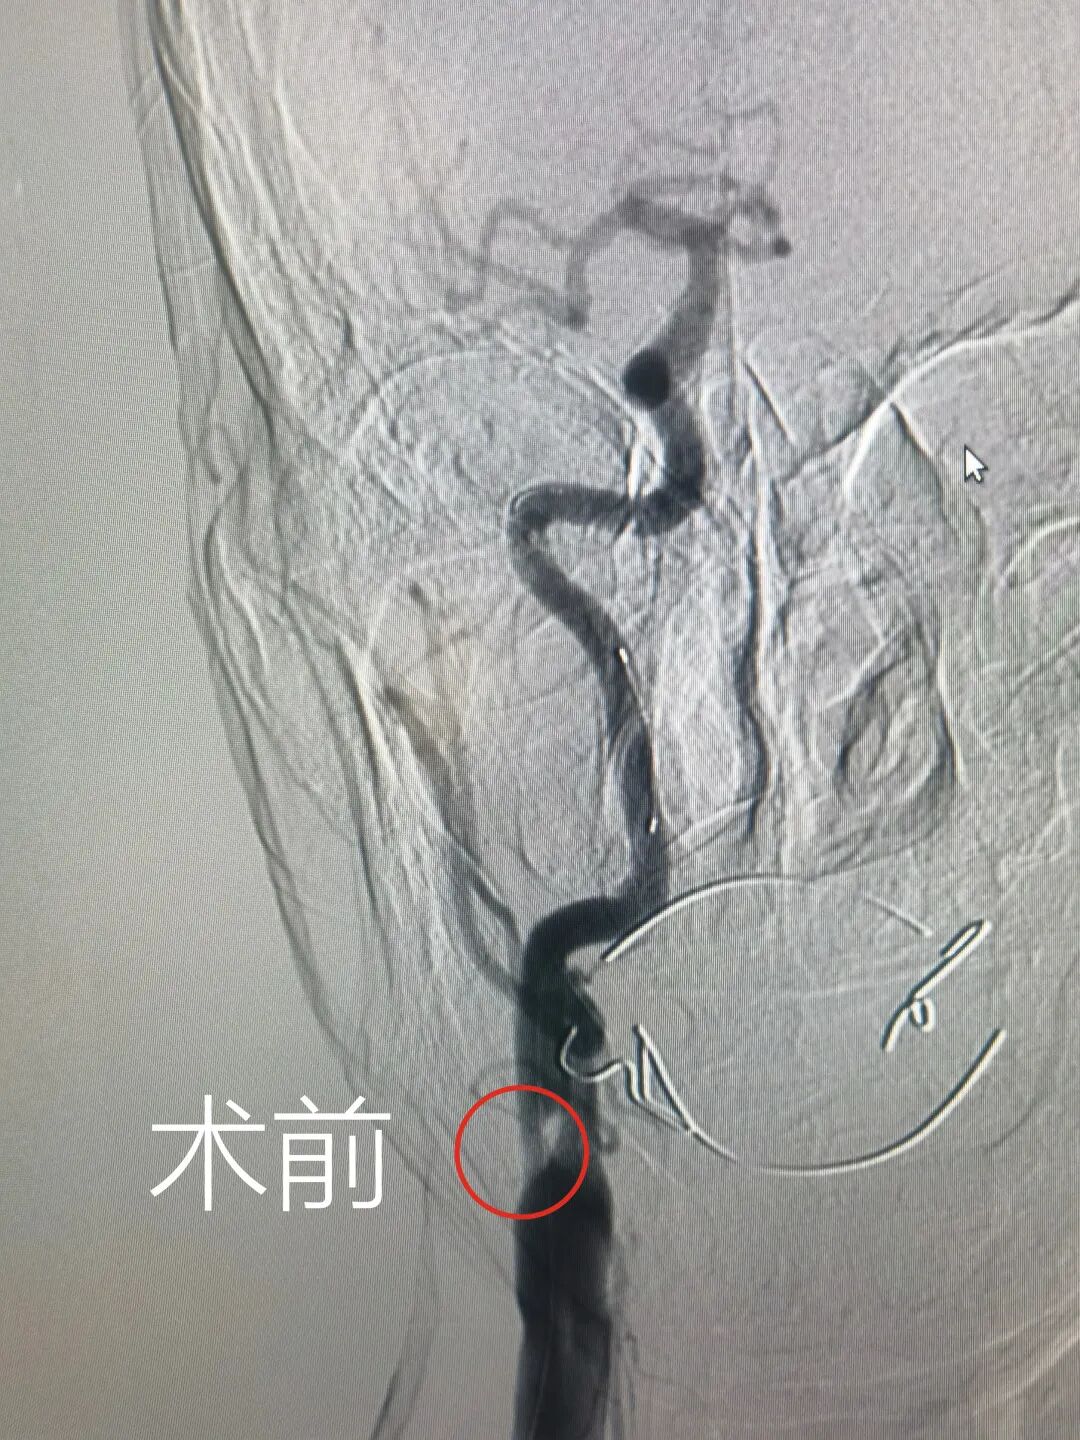

患者李某某,以急性脑梗死入住县医院神经内科。入院后经抗血小板聚集、改善脑血液循环等对症治疗,患者的病情得到了有效控制。进一步完善颅脑核磁、血管超声等相关辅助检查,初步了解了患者颅内动脉的病变情况。患者入院第3天即完成脑血管造影检查,明确了责任动脉狭窄病变的严重程度,患者右侧颈内动脉存在严重狭窄,颅内供血受到严重影响,再次出现脑梗死的风险较大。

县医院神经内科纪裕伟主任、奚继明副主任带领科室医护团队,对患者病情进行了详细讨论,认为单纯药物治疗效果欠佳,应及时采取颅内血管支架植入手术,减轻再发脑梗死风险。患者入院第6天即完成血管支架植入术,手术取得圆满成功。术后造影显示支架形态良好,无明显残余狭窄,颅内血流明显改善。